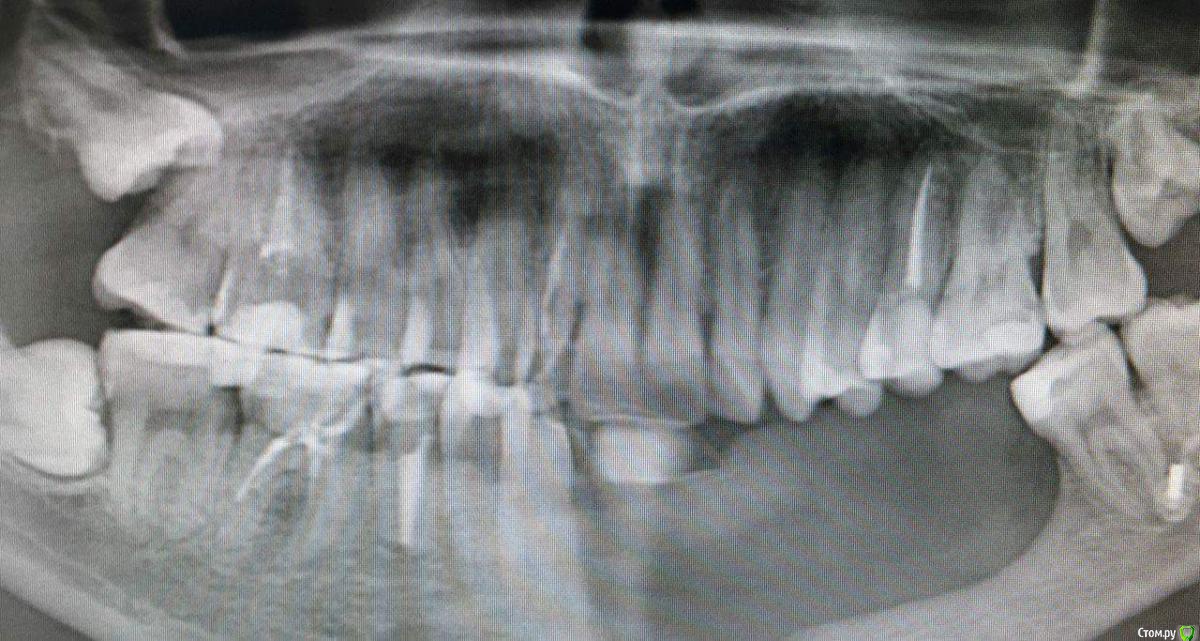

martynyukm Опубликовано 10 октября, 2016 Поделиться Опубликовано 10 октября, 2016 Здравствуйте, у меня отломался кусок зуба на нижней челюсти. На снимке второй после з.мудрости. Там когда-то была киста. Стоматолог утверждает,что зуб надо вырвать и ставить мост/имплант.тк нет смысла лечить то,что уже умирает. Мне 29 лет. Согласны ли вы? Спасибо. Ссылка на комментарий

DmitrySH Опубликовано 13 октября, 2016 Поделиться Опубликовано 13 октября, 2016 (изменено) Фото только так. Не вижу поводов для удаления. Требуется ревизия каналов с последующим протезированием. + лечение соседнего зуба (47)+ удаление 48Слева что-то планируется? Изменено 13 октября, 2016 пользователем DmitrySH 1 Ссылка на комментарий

martynyukm Опубликовано 13 октября, 2016 Автор Поделиться Опубликовано 13 октября, 2016 Нужно ли удалять лежачий 48 если он не мешает? Ссылка на комментарий

DmitrySH Опубликовано 13 октября, 2016 Поделиться Опубликовано 13 октября, 2016 Нужно ли удалять лежачий 48 если он не мешает? Мешать он не будет, седьмой только угробит.. потихоньку Ссылка на комментарий